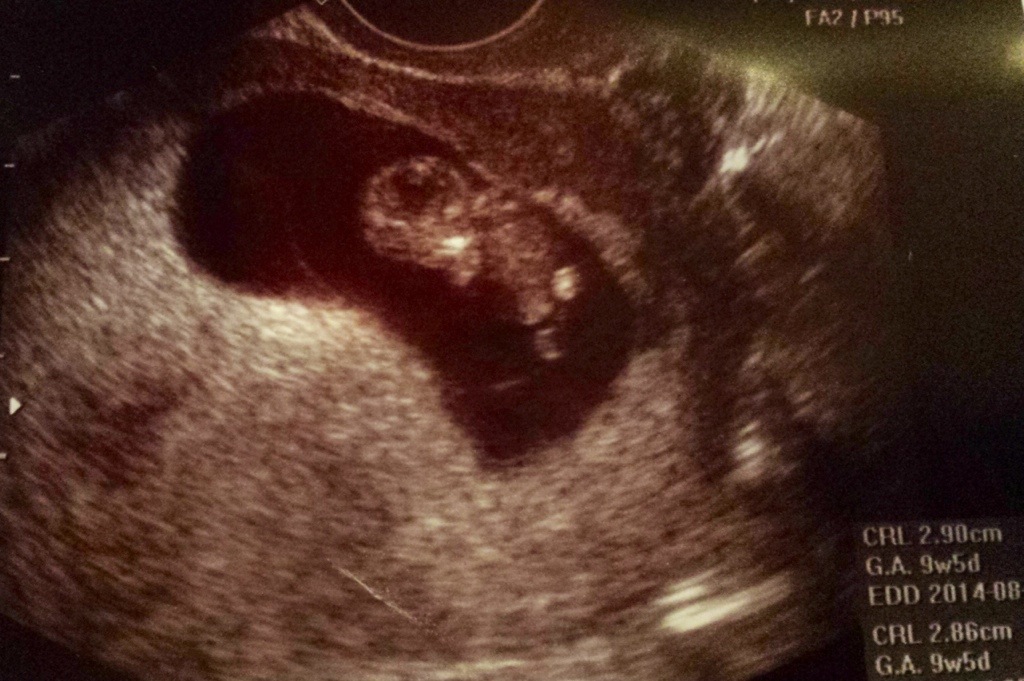

This past Thursday, January 9, 2014 was our first OB appointment. I was at the office for 3 hours, but I didn’t mind because I still can’t believe that I was even there. The sweet sweet nurse (who happens to be a friend and co-worker of my girlfriend who just had twins in December) met with me first and went thoroughly through my paperwork, then I met with my new OB (I use to see another Dr. in the group practice, but he has since retired) and again she was very sweet and thorough. My Dr. wanted to do another ultrasound (I had to ask if it was safe since it was my third one in about 2 1/2 weeks) and I got to see the babies again! Unfortunately, Hubby had to work and was unable to make it to this appointment. Baby B was dancing around like crazy, they both have little hands and feet now and I swear that Baby B was fist pumping. Lastly I had my blood drawn, I had to get poked twice, the first phlebotomist couldn’t get my blood flowing and sent me out into the waiting area with a glass of water, second time was a charm. Thank goodness!

More pictures of the little ones:

Baby A-Head up

Baby B-Head down